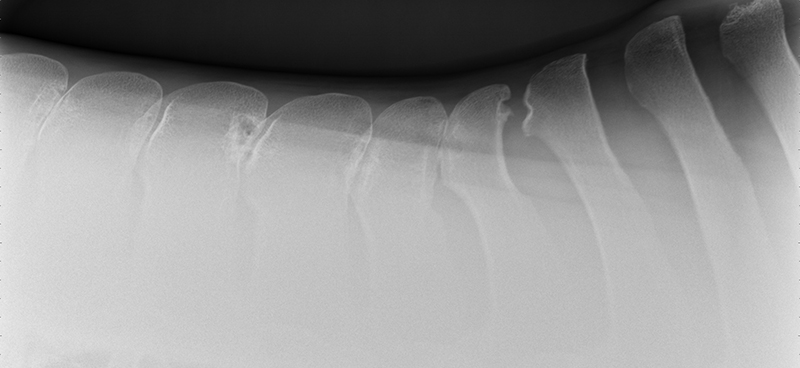

Kissing Spines, more scientifically known as impingement of the dorsal spinous processes, is a condition that has grown in relevance and impact throughout the last two decades with improved diagnostics and education. It’s hard not to feel a horse’s pain after taking just one look at an x-ray that indicates Kissing Spines. The condition can diminish athletic performance and render a horse unusable in severe cases, while other cases with the ugliest x-rays can experience no pain or performance implications. While still shrouded in some level of mystery, Kissing Spines is known to be conformational and most likely genetic. When spinous processes are conformationally close together they will inevitably contact, with that continual contact causing the modeling changes that are classically seen on radiographs.

Though Kissing Spines can be seen clearly in diagnostic imaging, truly understanding the nuances of the condition and how it can vary patient-to-patient is where things become less well-defined. Dr. Cliff Honnas, equine veterinarian, surgeon and founder of the widely respected Texas Equine Hospital in Bryan, Texas, is a sought-after authority figure in all things related to this condition, especially concerning its surgical treatment. “Kissing Spines is a condition where the dorsal spinous processes are too close together,” he explains simply. “These are the bones that make up the backbone of the horse directly underneath the saddle.” Normal horses should typically have a five millimeter or larger space between those bones, depending on the breed and size of the animal in question. In Kissing Spines cases, however, that space can be minimally to drastically narrowed until those bones are close together, touching or overriding.

While there are numerous conditions impacting the equine back, the diagnosis of Kissing Spines has increased fairly dramatically in recent years thanks to improved diagnostic techniques coupled with a greater focus on veterinary education. “Depending on who you choose to believe in the literature, Kissing Spines along with dorsal articular facet arthritis will account for 50 to 70 percent of orthopedic back problems,” says Dr. Kent Allen, sports medicine practitioner, founder of Virginia Equine Imaging, FEI Olympic-level veterinarian, current Vice President and Executive Director of ISELP and Chairman of the USEF (United States Equestrian Federation) Veterinary Committee. “The horse, which of course has a horizontal back as opposed to a human’s vertical back, doesn’t have disk problems like we do but rather has bony orthopedic problems that impact the way they bend, extend and jump, such as Kissing Spines and arthritis of the dorsal articular facets,” explains Dr. Allen. “In terms of Kissing Spines specifically, its location is most commonly from the base of the withers back to the thoracolumbar junction, from T16 back to L2-3. In contrast, arthritis of the articular area will often occur further back, about three inches forward to three inches behind the rear of an English Saddle.” While the general location and disease process have become more solidified, the clinical presentations exhibited by affected horses are wide-ranging and can create significant diagnostic and treatment challenges for veterinarians.

A condition where the dorsal spinous processes are too close together. Typically horses have about a five millimeter space between those bones; however, in Kissing Spines cases, that space is narrowed until those bones are close together, touching or overriding.

While the clinical signs of Kissing Spines can be ambiguous, Dr. Allen is quick to point out that not all horses with radiographic evidence of the condition display outward signs. “It's often a question of when this condition presents or if it presents. If we’re talking about a western pleasure horse or a horse that doesn’t ever jump over 2 feet 6 inches in its life, the animal may have Kissing Spines and never present. A look at the data on hundreds of horses with back pain revealed that the average age of presentation of back pain was about 6.5-years-old.”

While horses may be genetically predisposed to Kissing Spines and present clinical signs on an x-ray as early as 2-years-old, there are a great number of factors that go into determining if that horse will ever become clinical, including its level of training and specific discipline. Horses performing a sport that requires a high amount of flexing and bending of the back will oftentimes have increased odds of developing clinical symptoms of Kissing Spines in comparison to low-impact or more leisure-based sports — think of a cutting horse versus a horse primarily used on the trail. “A common situation is that we’ll see a horse come in for a pre-purchase exam, and since we’ll routinely do a back x-ray now, we’ll often see some degree of Kissing Spines,” says Dr. Honnas of a frequent and tough place that equine veterinarians find themselves in with potential buyers. “This could mean that space between those bones is reduced but very often not actually touching or overriding. We can also see horses that have tremendous Kissing Spines on an x-ray, but clinically are virtually normal and have no history of back pain. It makes it very difficult to decide on a pre-purchase exam what to recommend to the potential buyers in terms of their risk. This can be a top-end horse, doing its job well and with no disability. We’ll pick up Kissing Spines to some degree on the x-ray, and it’s impossible to state with certainty that horse’s risk of developing symptoms in the future.”

Following a thorough whole-body physical examination and a more specialized motion evaluation, the next step in a suspected case of Kissing Spines is to confirm the diagnosis with imaging. Drs. Honnas, Story, Williams and Allen are all significant proponents of the importance of those initial examinations prior to performing imaging. “I tell my clients, ‘I can x-ray your horse's back and look for things like Kissing Spines, but that could be just a tip of the iceberg,’ ” says Dr. Williams. “That comprehensive evaluation is absolutely necessary to form a complete picture.”

There are two primary diagnostic imaging methods that deliver the clearest picture — literally and figuratively — when dealing with a potential Kissing Spines case. “I teach combined imaging using x-ray and ultrasound to look at as much of the tissue as possible,” says Dr. Williams of his approach. While Kissing Spines can oftentimes appear clearly using x-ray alone, the use of this combined imaging approach delivers the most definitive diagnosis possible. “Ultrasound is the most sensitive tool to observe surface detail. It reflects off of bone. You can't see through it, but if the bone surface is uneven, it will tell you that. On an x-ray or a radiograph you can’t pick that up unless you get the perfect view,” says Dr. Williams of one reason he brings ultrasound into the equation. Another attribute of ultrasound is its ability to look at the supraspinous ligament, multifidus muscles and the facet joints, which are placed further down at the base of the spinous processes. “I talk about ultrasound surveys,” says Dr. Williams. “I don't just look with the ultrasound, then find something and walk away. I survey the back from the withers all the way back through the lumbar region. This gives me all of the information, and I can then better determine whether the horse has Kissing Spines alone, if the case is surgical and if there’s something else at play in addition to the Kissing Spines.”